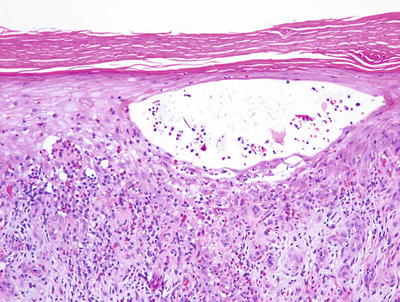

1.2.2 Histology

Histologic features of dyshidrotic eczema are nonspecific. The only distinguishing feature from other spongiotic processes is the acral location for this eruption (Fig. 1.5). Parakeratosis is present (except in very acute lesions) overlying an irregularly acanthotic epidermis with focal spongiosis that can range from slight to marked changes [34]. Collections of Langerhans cell microabscesses are seen in most cases (Fig. 1.6). Within the dermis, there is an infiltrate of lymphocytes and eosinophils may be present. Late lesions may demonstrate only minimal spongiosis and are indistinguishable from lichen simplex chronicus. In most cases, a PAS stain is recommended to exclude acral fungal infection, as the histologic changes may be identical .

Fig. 1.5

Acral skin demonstrating spongiotic dermatitis with microvesiculation is present in dyshidrotic eczema